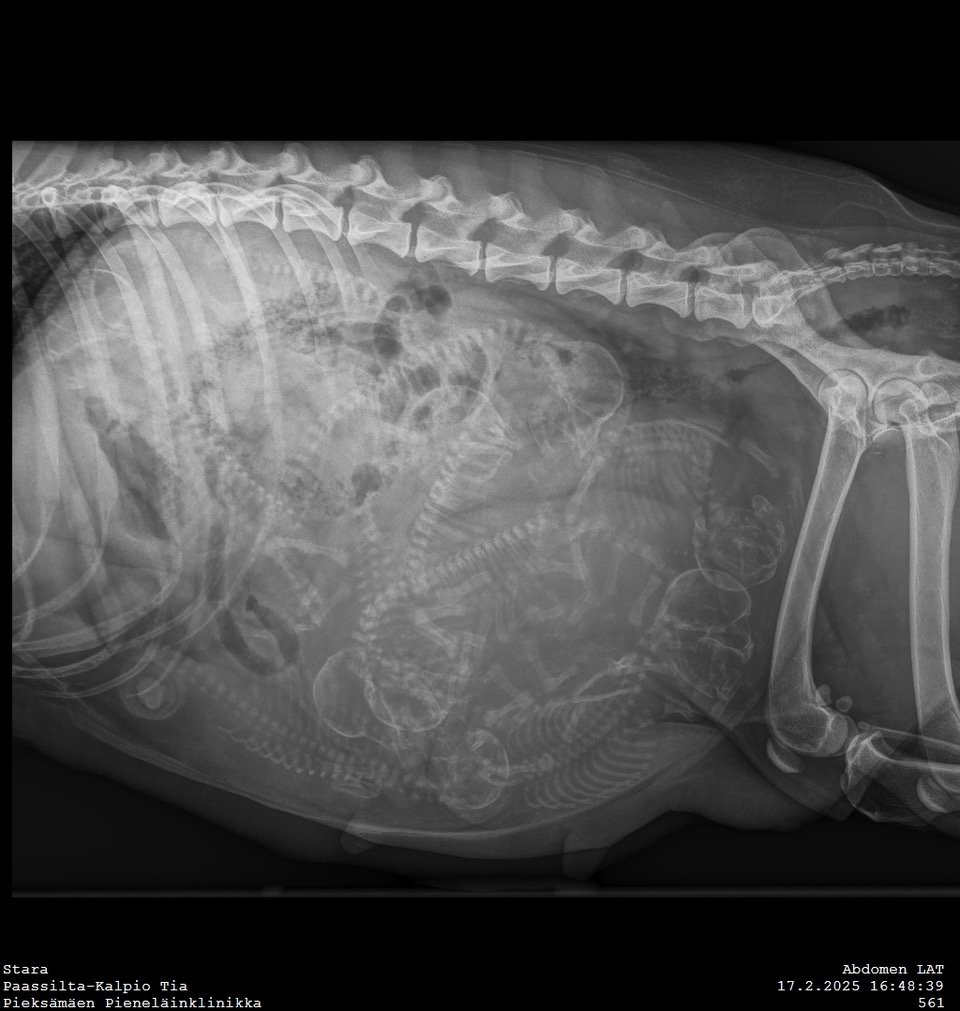

Tiineysröntgen

17.02.2025 | League of Legends-pentue